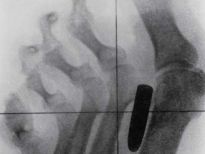

Bu röntgenler gerçek!

İki çatalı, bir tükenmez kalemi ve diş fırçasını yutmuş bir hasta.